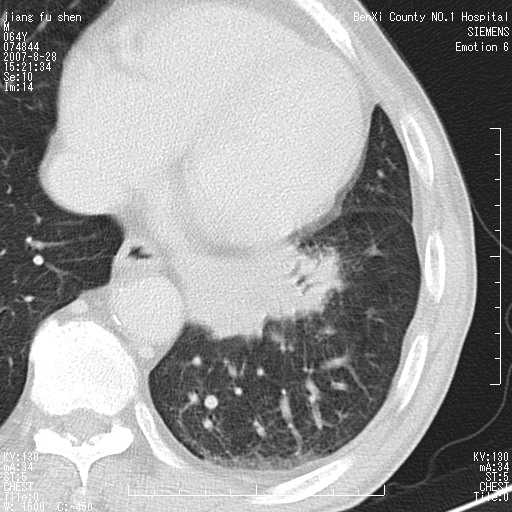

男、64、咳嗽、发烧一周、左肺呼吸音稍弱。既往肺结核,右手结核。

本次扫描患者未带原片,左肺下叶发现病灶。左肺上叶空洞,5组淋巴结肿大,1cm左右。

追问病史三月份ct扫描左肺上叶空洞,医大诊断肺结核。

平扫20-33hu

增强31-33hu

1分半44-52

2分55-67

左肺下叶前内基底段支气管明显偏心性狭窄,周围分叶状肿块,伴有阻塞性肺炎,支持肺癌可能性大。

考虑左肺中央型肺癌并阻塞性肺炎

病灶边缘可见多量较长棘影及纤维条索状影,除外病灶边缘较光整,病灶有分叶表现,但多表现为较浅分叶,且向周围伸出之叶多呈尖角改变,且边缘较光整,病灶增强呈中度延时增强,且早期及中期仅轻度增强,结合患者病史,多考虑继发型肺结核,炎性增殖灶形成,不除外肺癌

左下叶支气管变窄,管腔光滑。软组织形状不规侧,分叶呈角形。结合病史考虑结核可能性大。肺癌不除。

左肺下叶中央型肺癌

支持 左下中央型肺癌可能性大。

左下中央型肺癌可能性大